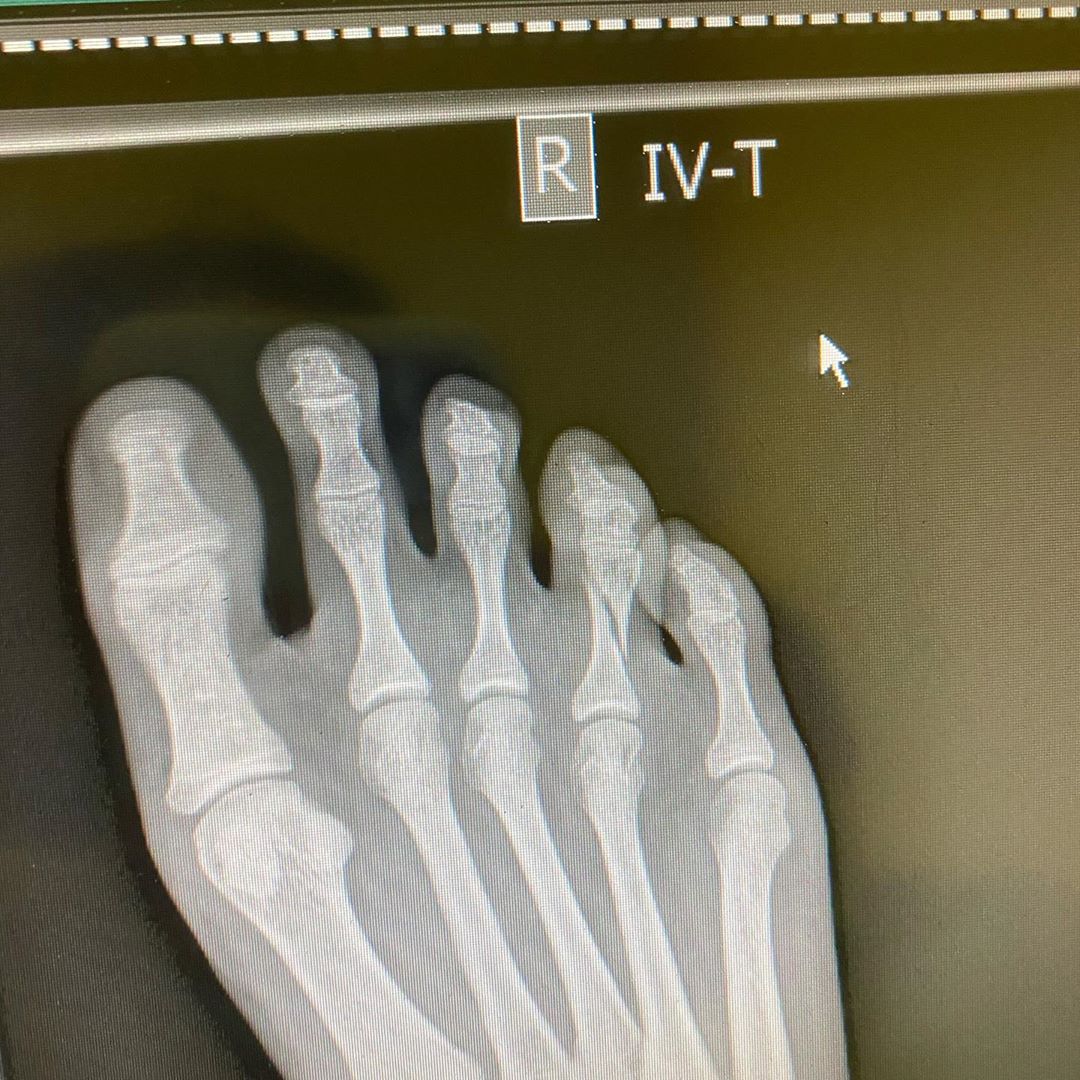

Під час прогулянки по місту дівчина зламала палець на нозі

Причому приводом для цього стала отримана Машею травма - під час прогулянки по вечірньому місту з коханим вона примудрилася зламати палець на нозі. Їй довелося звернутися в лікарню, де дочці артистки наклали на праву ногу гіпс. Бойфренд весь цей час був поруч і підтримував дівчину, а також катав її на візку по коридорах лікарні.

Маша Полякова зламала палець на нозі і показала фото з лікарні (фото: instagram.com/mashapolyakova)